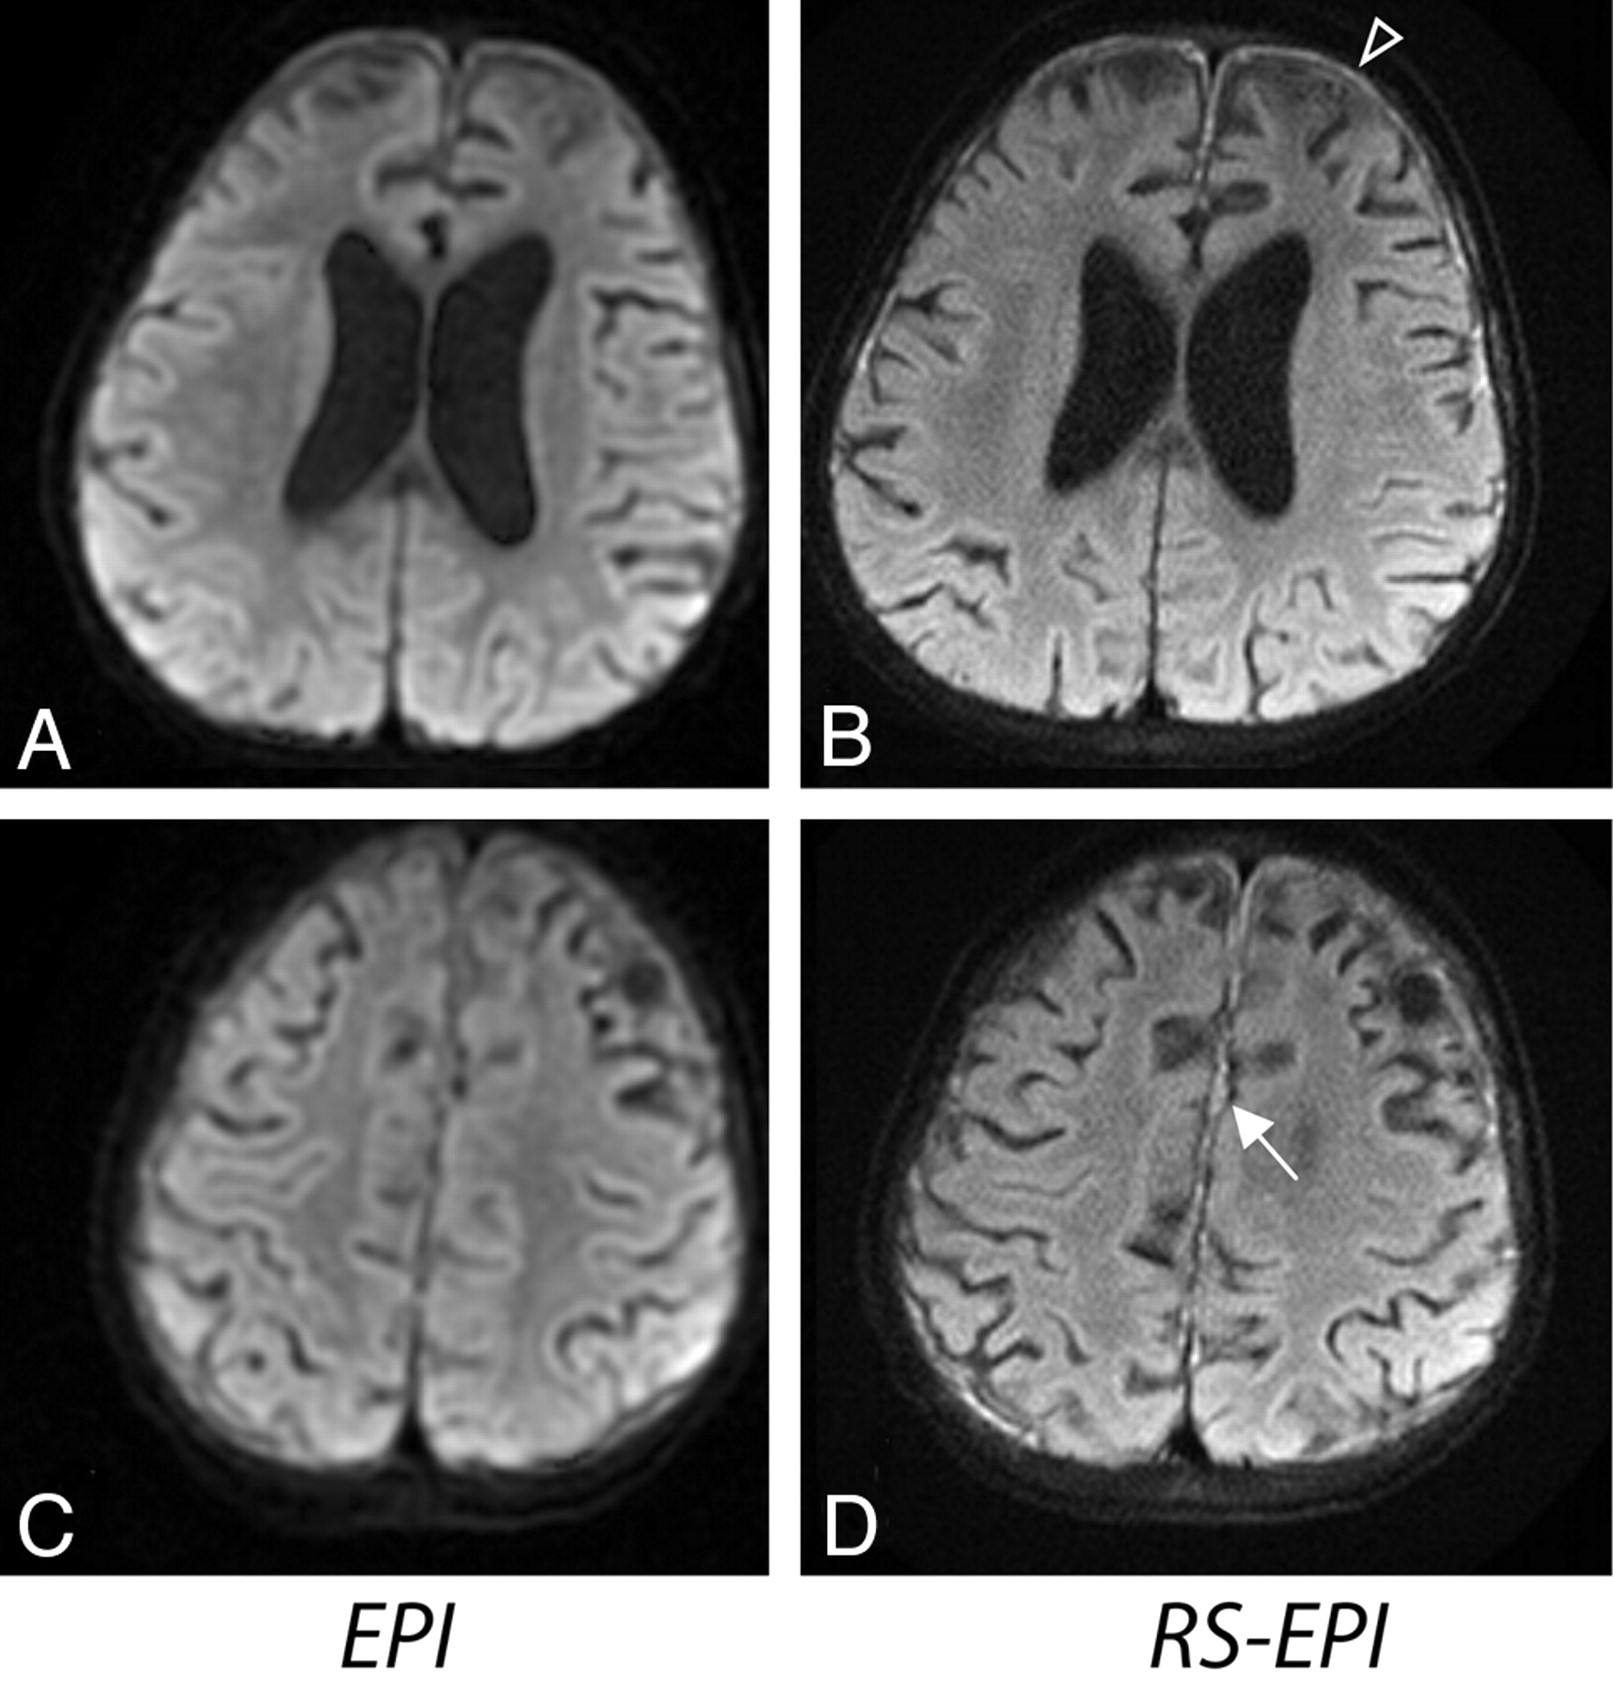

RS-EPI also reduced distortion in areas adjacent to tissue-air or bone interfaces from signal-intensity pile-up effects (Fig 6A, -B) and gave increased diagnostic confidence in areas adjacent to the auditory canal in a patient with tumor (Fig 7). In several patients, EPI had elevated gray/white matter contrast on iso-DWI due to a more pronounced T2 shinethrough effect from the longer TE of EPI as shown in Fig 8 (note that this did not occur for RS-EPI even though RS-EPI used twice-refocused diffusion preparation which prolongs TE). These equivocal signal-intensity high intensities occasionally led to a decreased diagnostic confidence level.

Two sections from a patient with diffuse infiltrating anaplastic astrocytoma (a 14-year-old girl). A and B, DWI shows areas of increased cellularity (open white arrow). C and D, Areas of increased signal intensity on EPI (white arrow) suggest the possibility of cortical and subcortical tumor involvement, which may be seen with gliomatosis or diffuse infiltrating glioma. Reduction of distortion in RS-EPI shows a normal cortical ribbon. Also, the open arrows show areas of increased distortion on EPI compared with RS-EPI.

Two sections from an 8-year-old female patient. A, Distortion artifacts on EPI could be confused with subdural hemorrhage or empyema. This artifact disappears on RS-EPI (B). A,C, Elevated contrast on EPI, not appearent on RS-EPI (B,D), could be confused with diffuse cortical ischemic injury, encephalitis, or even seizure-related changes.